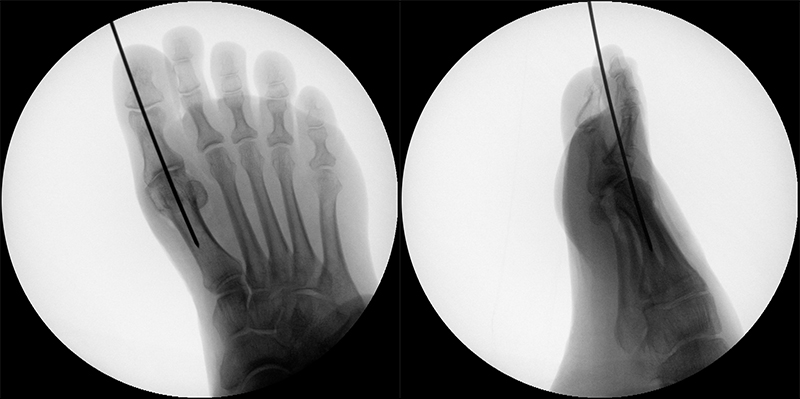

Zum Lesen der Bildbeschreibung und zur Vollansicht bitte das Bild anklicken (Foto: M. Walther).

Zum Lesen der Bildbeschreibung und zur Vollansicht bitte die Bilder anklicken (Fotos: M. Walther).